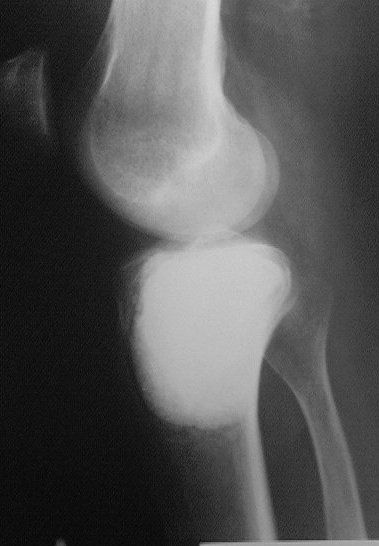

Около года назад больному 25 лет по поводу литической опухоли мыщелка б\б кости ( ОБК?)с выраженным болевым синдромом была произведенарасширенная открытая биопсия, экскохлеация опухоли.

В связи с неясностью диагноза до операции и отсутствия аллокости в тот момент интраоперационно было выполнено экспресс протезирование дефекта мыщелка акриловым цементом. Верхней стенкой дефекта была визуально неповрежденная суставная поверхность. Хрящевая пластина провисала - была выведена на уровень и "подперта" цементным спейсером. Больной осмотрен через год - ходит не хромая, сустав абсолютно спокойный, рентгенологически процедива опухоли нет. Хотелось бы услышать предложения по пластике дефекта - сроки, вид материала. Честно говорябоюсь трогать хрящ повторно.

Случай очень интересный! Увидеть бы снимки до операции. Можно обсудить состояние хряща "на цементе"-за счет чего он жив или там все-таки дефект? Щель сустава хорошая. Есть ли возможность проведения МРТ у больного?

Согласен с предыдущими мнениями. Данных за рецидив нет, функция приличная,пациент доволен. Зачем создавать лишние проблемы себе и больному?! Необходим только клинико-рентгенологический контроль в динамике. Кстати, метод замещения таких дефектов цементом используется часто за рубежом, результаты описаны в доступной англоязычной литературе, в частности - в Clin. Orth. и JBJS.

Субхондральное эндопротезирование костным цементом при доброкачественных опухолях давно используется в институте им. Вредена. Редко бывают рецидивы (костный цемент, полимеризуясь, нагревается до 70 градусов). Сроки наблюдений благополучного исхода более 20лет.